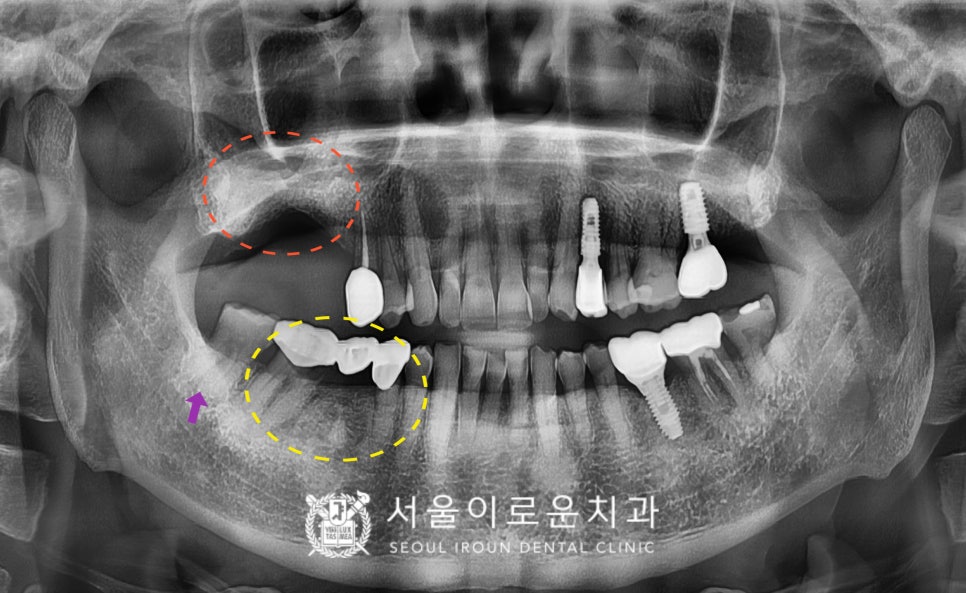

정밀한 검사를 위해

파노라마 사진을 촬영해

확인해 보았더니

노란색 동그라미의

기존 브릿지 보철물 치아 중

두 번째 큰 어금니(#47)가

충치로 인해 치아의 머리 부분과

뿌리가 분리가 된 상태였습니다..!

안타깝지만 살려 쓰기에는

예후가 좋지 않아

발치가 필요한 상황이었는데요.

다행히 두 번째 작은 어금니(#45)는

검진 시 특이 소견이 없어

크라운 치료를 진행하기로 하였답니다.

두 번째 큰 어금니(#47)는 발치하면서

동시에 어금니 자리에 임플란트 2개를

식립하기로 계획하였고,

바로 뒤의 사랑니(#48)도 함께

발치하기로 하였습니다.

그리고 오른쪽 위턱의 어금니는

상실된 상태로

임플란트를 같이 진행을 원하셨는데요.

상실 된 지 오래되어

뼈가 부족한 상황이라,

상악동 거상술을 동반한

임플란트 식립을 계획하였습니다. (2개 식립)